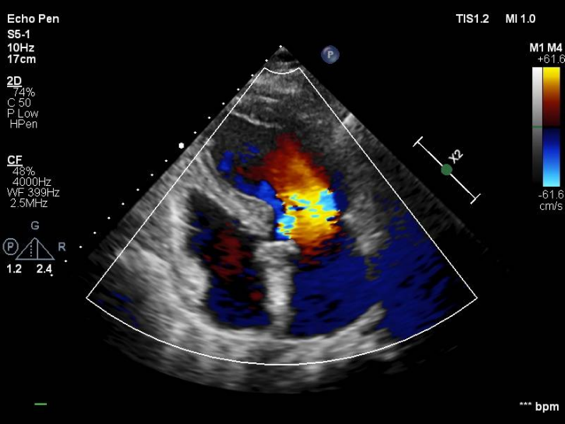

心脏超声

LVEF 35 %,主动脉瓣钙化,主动脉瓣三叶瓣,开放受限,闭合不拢,主动脉瓣峰值流速4.3m/s,峰值压差73mmHg,平均压差37mmHg,三尖瓣重度反流,TAPSE 13mm。